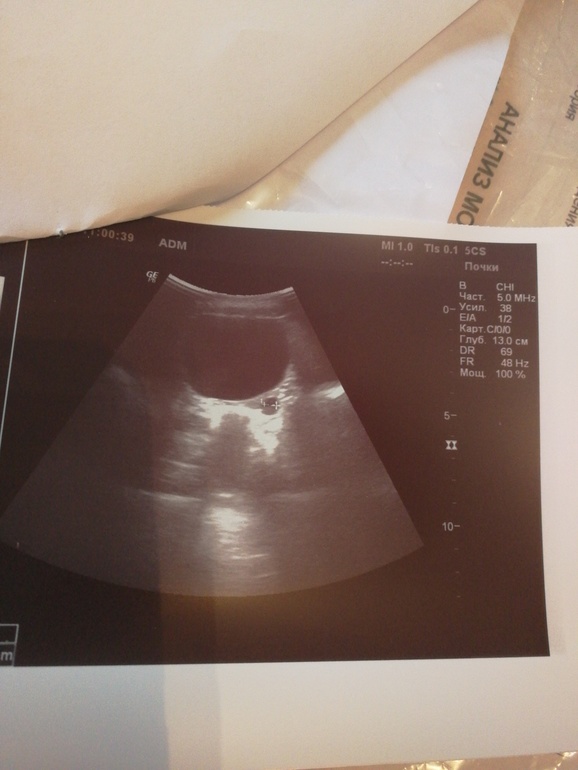

Добрый день! Помогите, пжт. Вчера сделали УЗИ девочке 1 год. Причина, что в бак посев мочи эшехерия коли 10 в 6. Периодически ыли плохие анализы мочи, ничем не лечились (бывал белок, лейкоциты повышены). На УЗИ выявили расширение дистального отдела левого мочеточника 5.5. При этом был полный мочевой пузырь и во время исследования девочка пила. Уролог считает, что надо в стационар для обследования. Читаю в интернете, роде нормальные размеры мочеточника. И разве не мог он быть расширен по причине полного пузыря? Спасибо!

Здравствуйте. Очень сложно комментировать не увидев самого исследования.